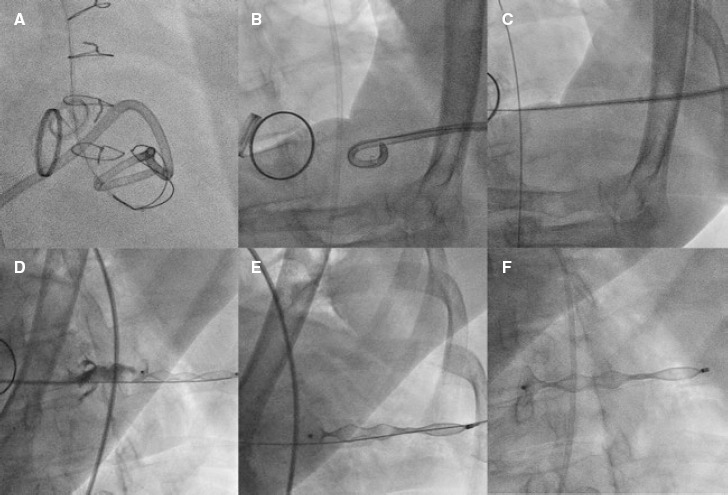

Percutaneous closure of left ventricular puncture after thoracentesis.